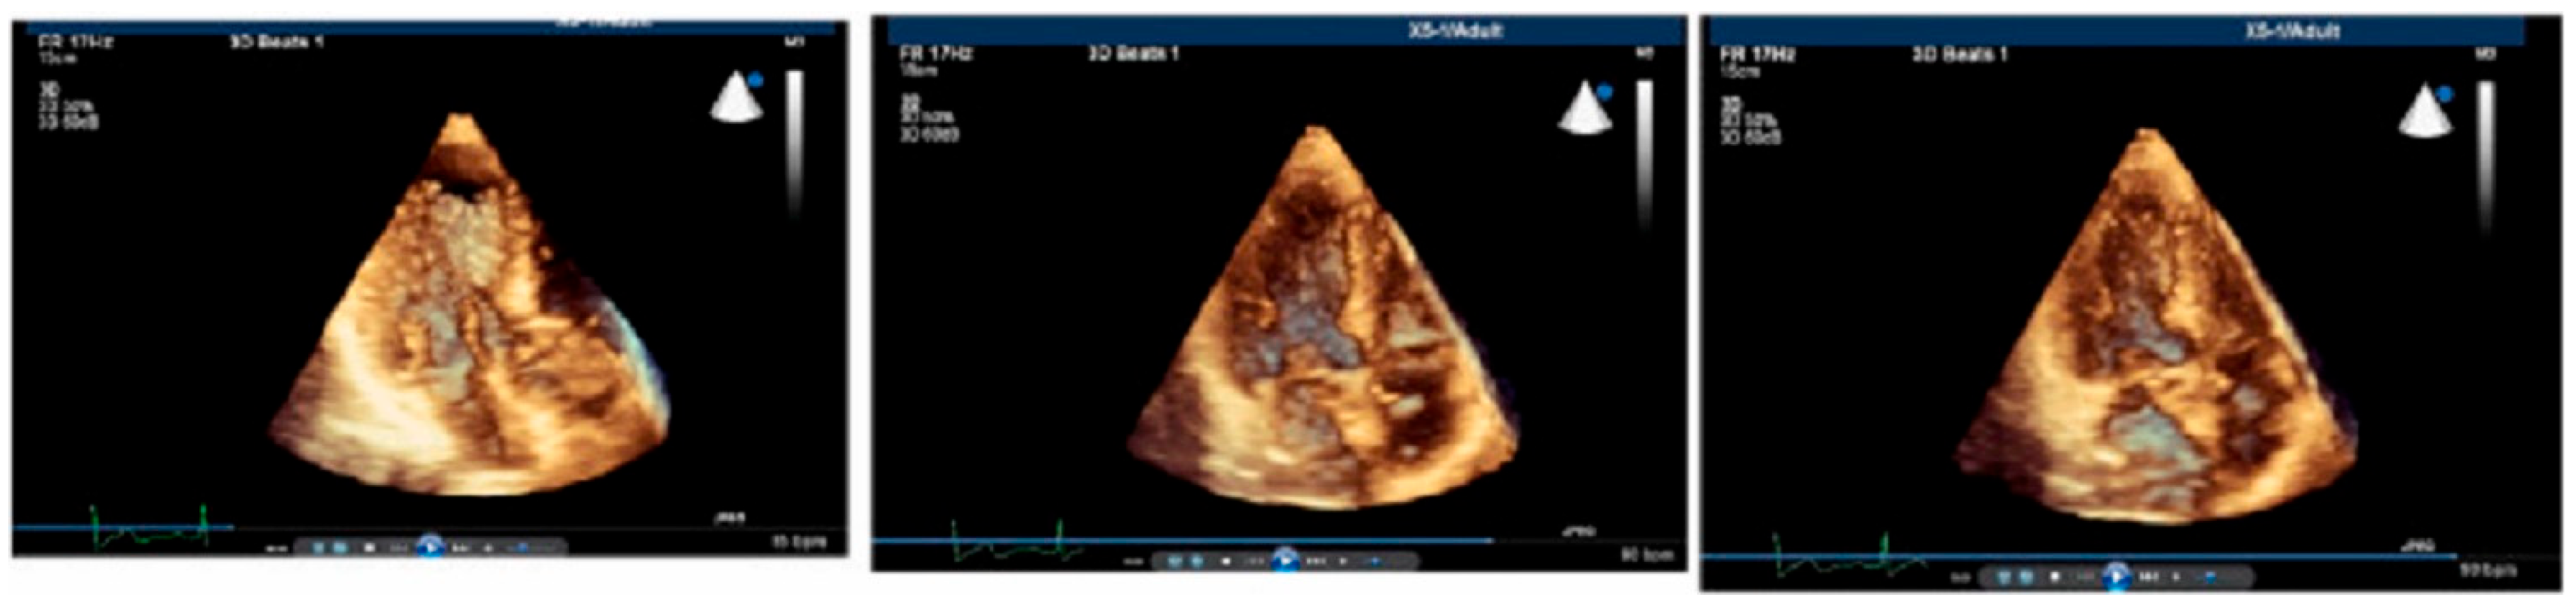

1.1. Real-Time Three-Dimensional Imaging

1.2. Stressed Heart Morphology

- Yalçin, F.; Shiota, T.; Odabashian, J.; Agler, D.; Greenberg, N.L.; Garcia, M.J.; Lever, H.M.; Thomas, J.D. Comparison by Real-Time Three-Dimensional Echocardiography of Left Ventricular Geometry in Hypertrophic Cardiomyopathy versus Secondary Left Ventricular Hypertrophy. Am. J. Cardiol. 2000, 85, 1035–1038. [Google Scholar] [CrossRef] [PubMed]

- Yalçin, F.; Shiota, M.; Greenberg, N.; Thomas, J.D.; Shiota, T. Real Time Three-Dimensional Echocardiography Evaluation of Mitral Annular Characteristics in Patients with Myocardial Hypertrophy. Echocardiography 2008, 25, 424–428. [Google Scholar] [CrossRef]